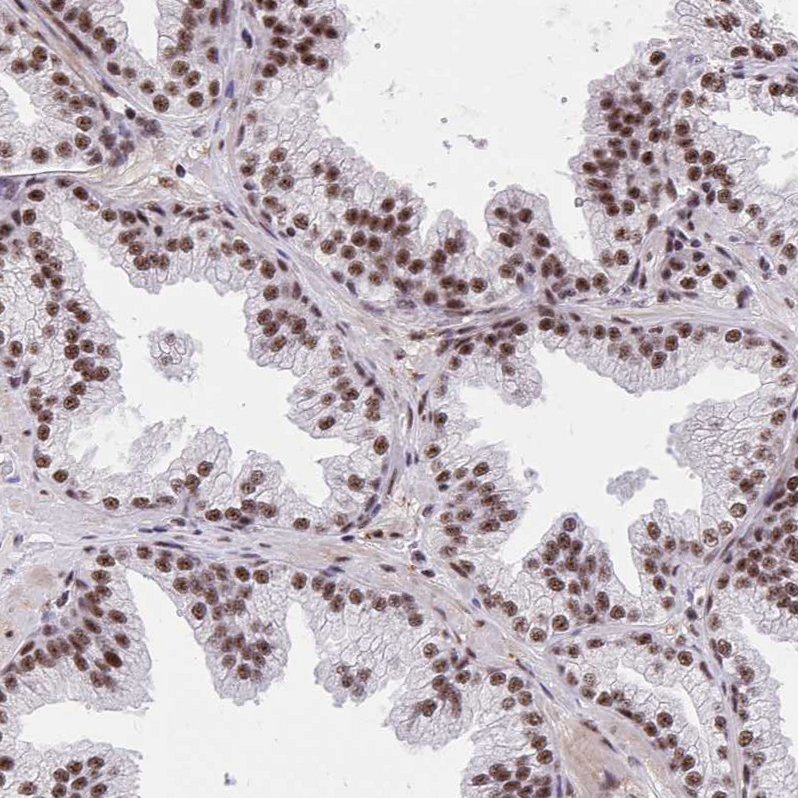

Immunohistochemical staining of human prostate shows strong nuclear positivity in glandular cells.